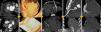

MethodsAll procedures were performed by experienced cardiologists or cardiac surgeons, using a Seldinger technique according to previously described protocols.17 CT guidance was obtained using a 64-slice scanner (Siemens SOMATOM Sensation, Erlangen, Germany) (Figure 1). Patients provided informed consent. During the procedure they were asked to breathe steadily and abstain from moving or breathing deeply. Local anesthesia with subcutaneous lidocaine was performed in every patient and light sedation (diazepam 5 mg orally) was administered when needed.

Use of computed tomography in pericardiocentesis. (a) Characterization and assessment of effusion; (b) determination of best entry point and needle orientation; (c) control of needle progression and relation with surrounding structures; (d) pigtail positioning; (e) final result and control of evolution.

Images of the whole thorax were acquired before the procedure and were analyzed with dedicated software (Siemens Syngo Viewer®). Parameters used by protocol were: tube voltage 100 kV, tube current 110 mAs, reconstruction with 0.75 mm sections, overlap 0.5 mm. Typical window width/level used during the procedure was 700/80. The best entry point and needle orientation were determined (Figure 1). We used an 18 gauge needle from the PeriVac™ kit (Boston Scientific®). After superficial needle insertion, new images of the area of interest were acquired. Needle orientation was corrected as needed and the needle was advanced under aspiration. New images were acquired as needed. When the pericardial space was reached, a drain (8.3F pigtail catheter from the kit) was inserted through a guidewire (J-tipped 0.035″×80 cm) and final images were acquired. When in doubt (due to limited pericardial width at the puncture site) a small amount of contrast (by protocol 5 ml diluted in 10 ml of saline) was injected to confirm an intra-pericardial needle position before dilation and drain insertion (Figure 2).